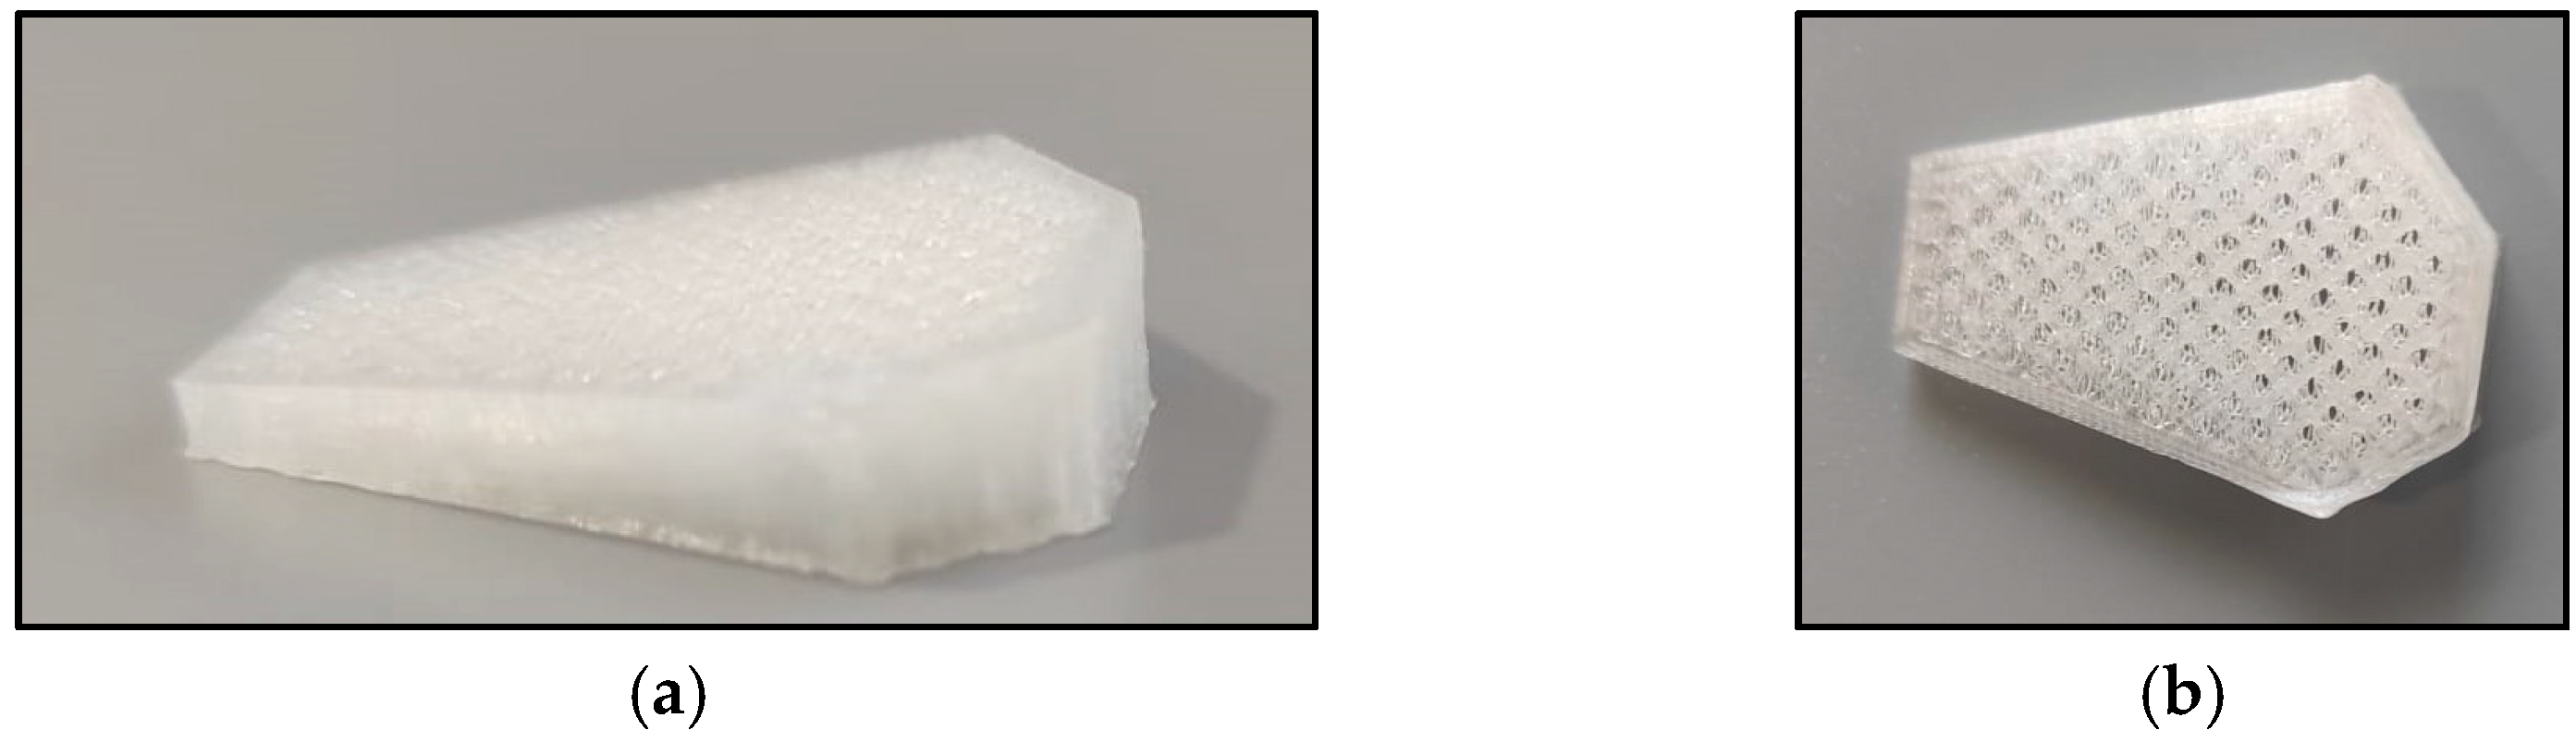

2. Materials and Methods

2.2. PRGF Fabrication

- Castilho, M.; Dias, M.; Vorndran, E.; Gbureck, U.; Fernandes, P.; Pires, I.; Gouveia, B.; Armes, H.; Pires, E.; Rodrigues, J. Application of a 3D printed customized implant for canine cruciate ligament treatment by tibial tuberosity advancement. Biofabrication 2014, 6, 025005. [Google Scholar] [CrossRef] [PubMed]

- Valiño-Cultelli, V.; Varela-López, Ó.; González-Cantalapiedra, A. Preliminary Clinical and Radiographic Evaluation of a Novel Resorbable Implant of Polylactic Acid (PLA) for Tibial Tuberosity Advancement (TTA) by Modified Maquet Technique (MMT). Animals 2021, 11, 1271. [Google Scholar] [CrossRef]